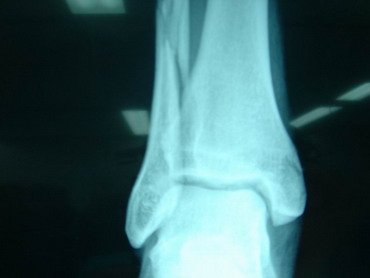

13 -5 -07 Durante el tercio de banderillas, de la lidia del 5º toro, ingresó en esta enfermería y fue asistido D. Pablo Hermoso de Mendoza de las lesiones que a continuación se especifican: Posible fractura 1/3 distal miembro inferior izquierdo con posibles afectación de tibia y peroné. Constantes normales. Miembro inestable, no dolor excesivo, ni frialdad distal, riego sanguíneo distal conservado, se inmoviliza con férula neumática y se traslada bajo control médico a clínica Sagrado Corazón de Sevilla. Pronóstico grave. Dr. D. Raúl Morales Maruri. |

14 - 5 - 07 El torero se interviene hoy a la 12,30 horas en la Clínica Sagrado Corazón de Sevilla. Se confirma diagnóstico provisional hecho en la enfermería de la plaza de Osuna. Fractura de tibia y peroné. Con las siguientes connotaciones: La fractura de peroné es completa y compleja consta de 4 fragmentos diferentes con desplazamiento de los mismos. es decir una fractura conminuta. La tibia presenta fractura maleolar con desplazamiento y además con respecto al tobillo existe una subluxación de la articulación debida a la rotura o explosión de la cápsula articular con desflecamiento de la misma. En resumen un cuadro complejo de tobillo inestable que precisa intervención quirúrgica inmediata. Se estabilizan las fracturas, se sutura la cápsula anterior, se reduce la subuxación, se administran factores de crecimiento y se inmoviliza extremidad. Pronóstico grave. Se estima un tiempo de recuperación de 90 días. Dr. Minguet. Dr. Periañez. Dr. Vaz. Dr. Morales |